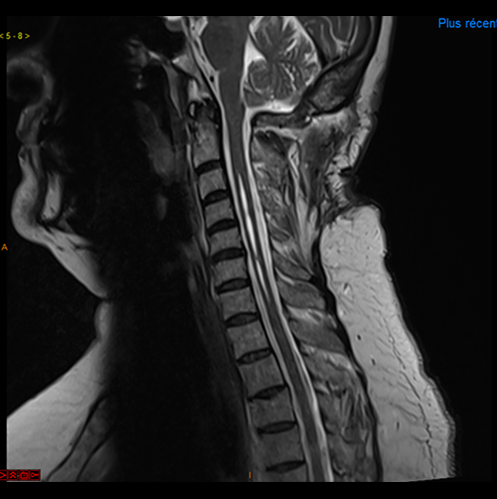

Malformation d’Arnold Chiari avec syringomyélie, post opératoire

Pré et post opératoire, disparition de l’engagement des tonsilles cérébelleuses et diminution de la syringomyélie

La chirurgie correspond donc à un élargissement du trou occipital permettant un repositionnement du cervelet et la levée de la compression du tronc cérébral. Le liquide cérébrospinal peut également reprendre un écoulement classique.